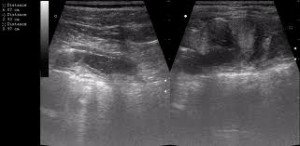

УЗИ Поджелудочной железы

УЗИ поджелудочной железы – это высокоинформативный метод диагностики заболевания, практически не имеющий противопоказаний. Ультразвуковая диагностика в Киеве производится к нашей Клинике.

Качественное оборудование клиники позволяет говорить о многих заболеваниях, которые просто не под силу рядовым УЗИ аппаратам. Своевременная диагностика и лечение залог крепкого здоровья.

Поскольку в медицине не бывает мелочей, провести УЗИ исследование поджелудочной нужно как можно более тщательно.

Если при УЗИ поджелудочной железы врач может оценить только размеры, структуру и этого не достаточно для обследования, могут быть применены лабораторные методы. Среди лабораторных методов – диагностика ферментов, анализ на сахар крови, мочи и т.д. Также помимо Ультразвукового исследования поджелудочной, рекомендуется проводить УЗИ печени и других органов брюшной области.